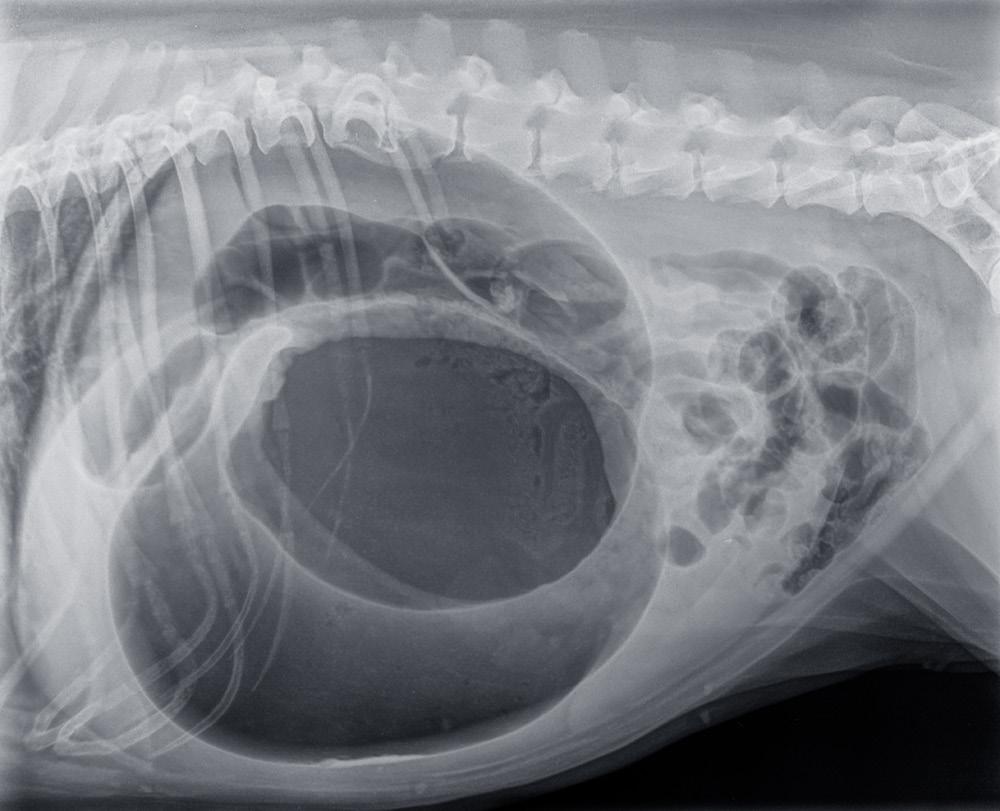

1. REDUCING THE RISK OF BLOAT

One of the most serious health concerns linked to rapid eating is gastric dilatation-volvulus (GDV), or bloat. This is a life-threatening condition in dogs where the stomach fills with gas and can twist. Large and deep-chested breeds, such as Great Danes, Weimaraners, and Setters, are particularly at risk.

While bloat can occur for multiple reasons, eating too quickly is considered a contributing factor. By slowing a dog’s eating pace, slow feeders may help reduce the likelihood of excessive air swallowing (aerophagia) and the subsequent risk of GDV.